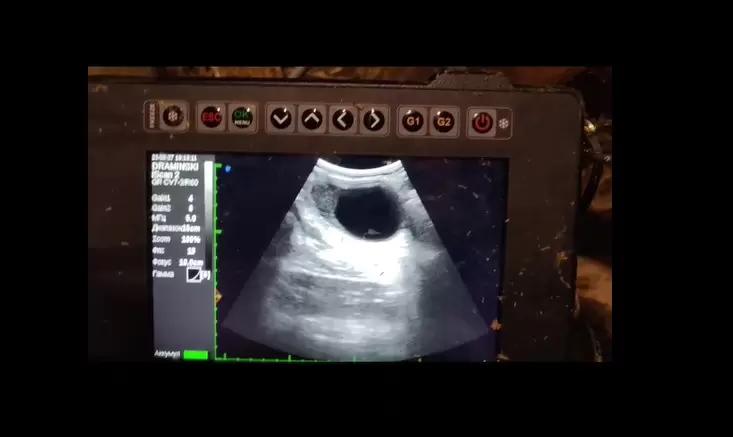

Вопросы из чатов: какая киста на УЗИ?